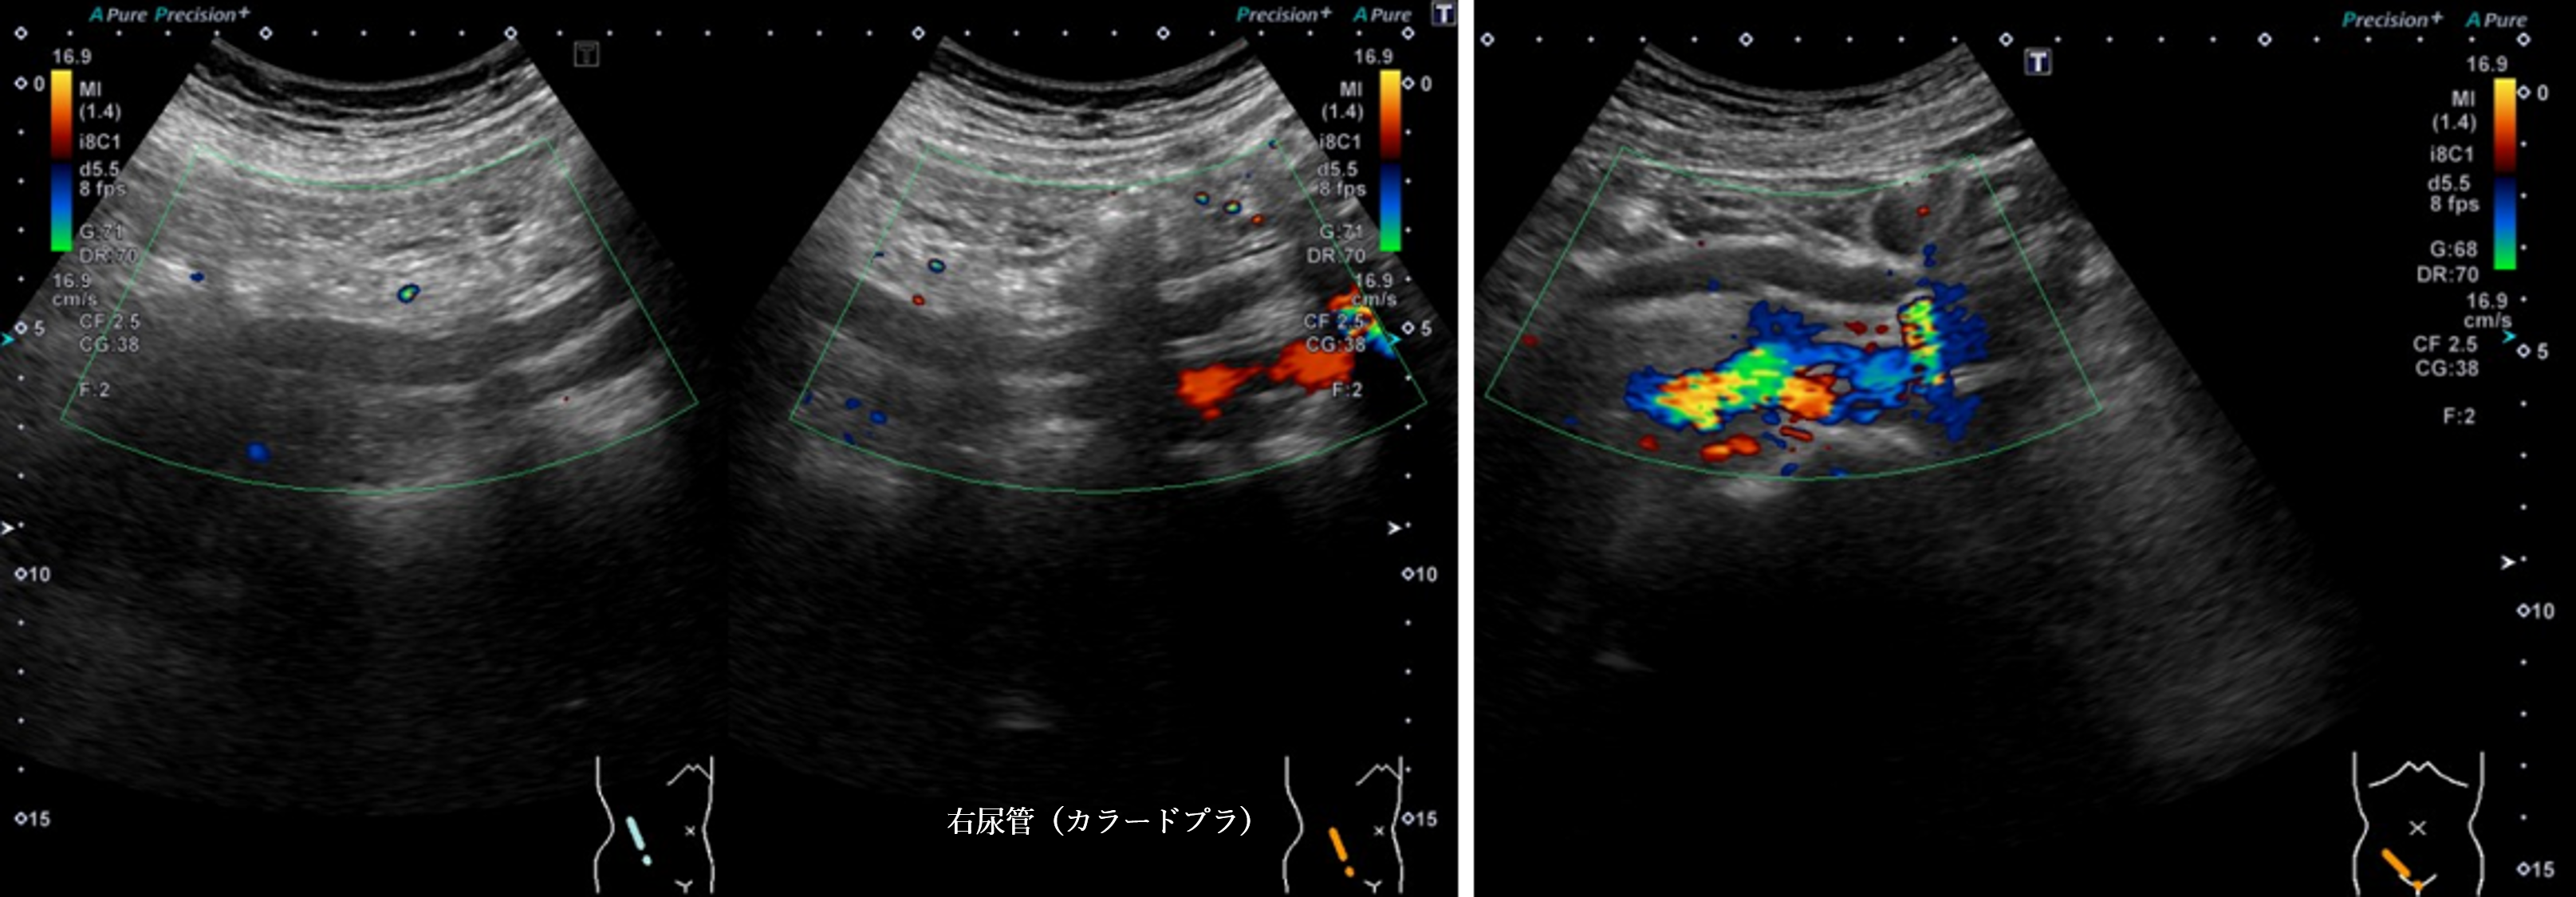

腹部超音波2 動画3 右尿管(No18-19_C)

腹部超音波2 動画3(No18.19_C)

① 右尿管内に充実性腫瘍像を認める

④ 右腎の腎盂拡張および右尿管拡張を認める

③ 尿管結石